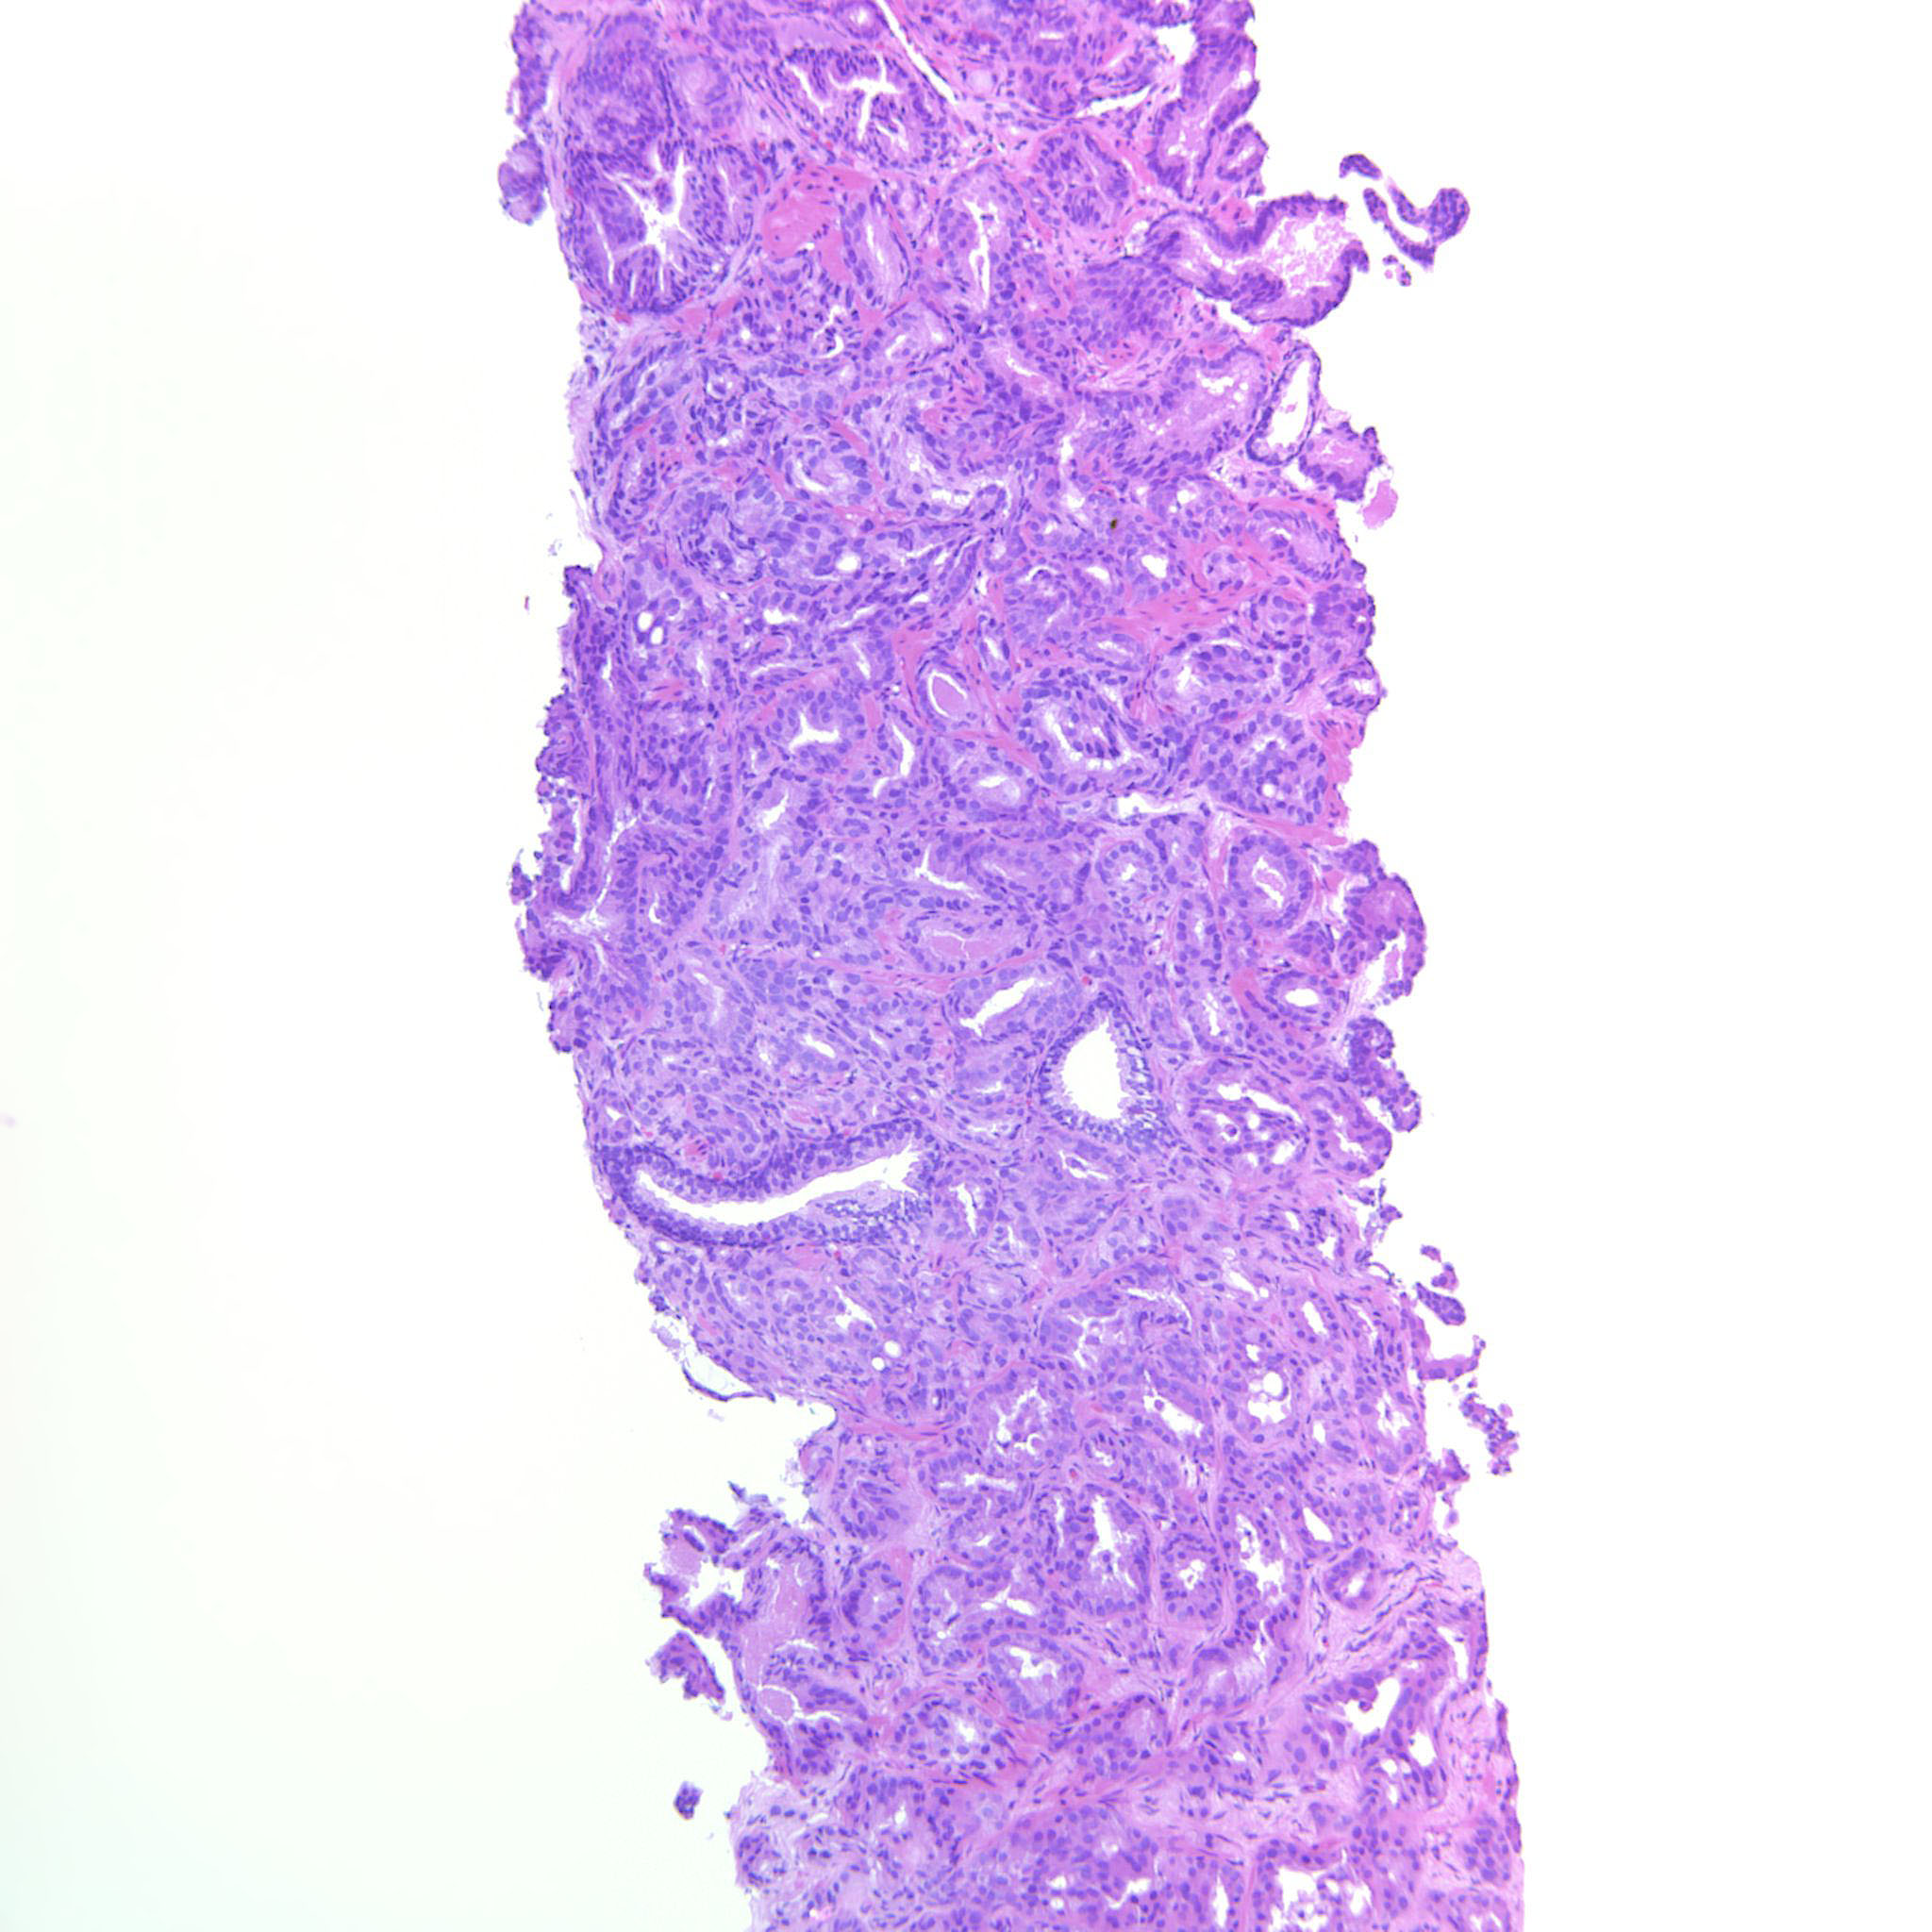

Prostate cancer grading

Case ID: 537